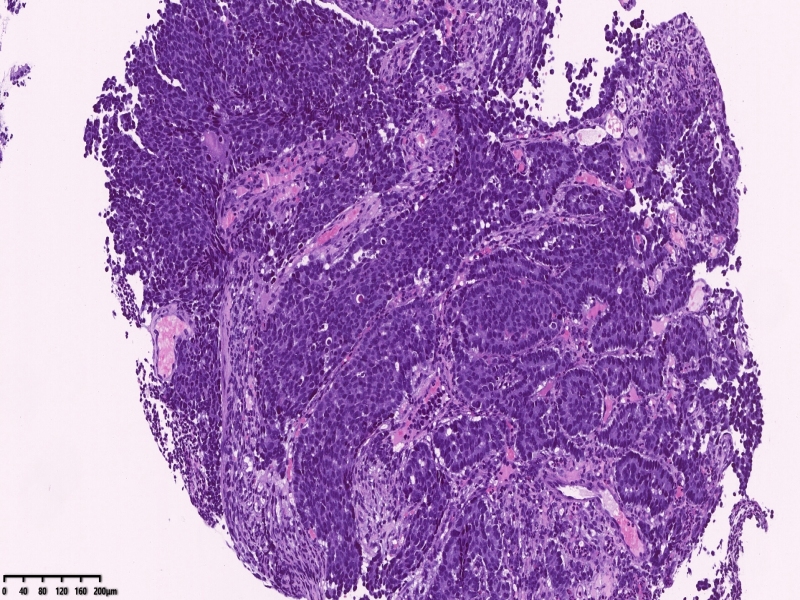

镜下所见:胃粘膜组织数块,炎症背景,其中3块固有层内可见细胞团,瘤细胞排列呈条索状迂回后呈巢状,巢的边缘瘤细胞呈栅栏状。细胞形态似柱状。

第一感觉考虑神经内分泌肿瘤?会诊考虑低分化腺癌。以前也遇到一个类似病例,贲门口占位,初步考虑神经内分泌肿瘤,但是神经内分泌标记均为阴性,最后考虑低分化腺癌。